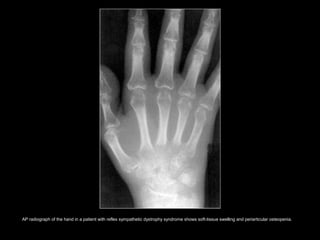

• RSDS : mediated by the sympathetic

nervous system and is characterized by

– aggressive osteoporosis,

– soft tissue swelling.

 The cause is usually traumatic, but the

disease may also be idiopathic.

AP radiograph of the hand in a patient with reflex sympathetic dystrophy syndrome shows soft-tissue swelling and periarticular osteopenia.